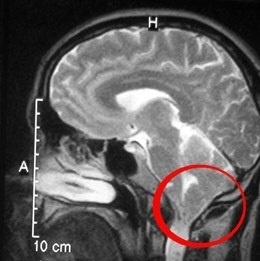

Аномалия Арнольда-Киари: MRI снимки